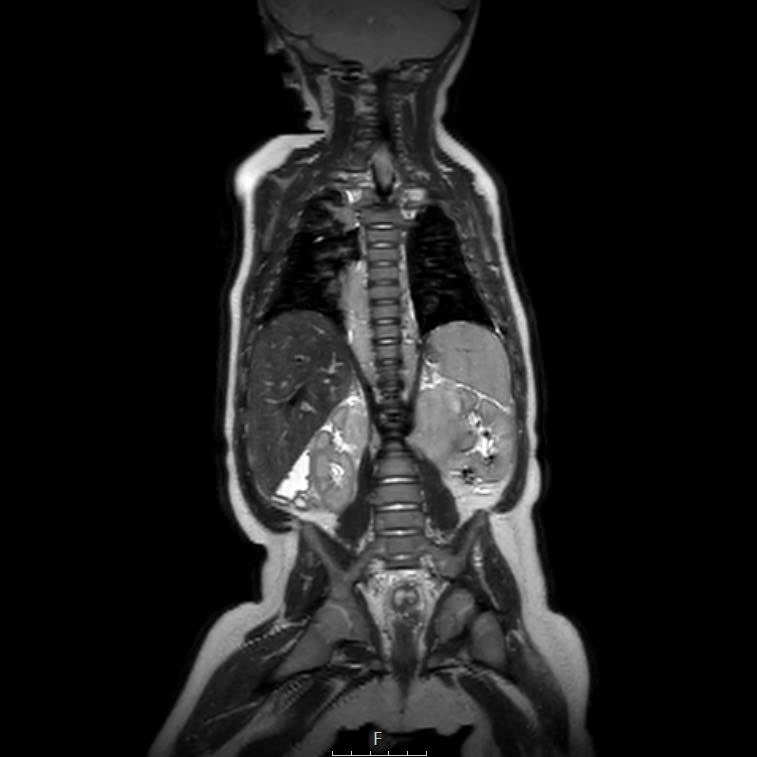

Cuộn qua chuỗi ảnh T2 theo mặt phẳng coronal.

Nghiên cứu các hình ảnh và sau đó tiếp tục đọc.

The findings are:

- Mass with encasement of the aorta and splanchnic vessels.

- Lan rộng dọc theo cột sống ngực nhưng không xâm lấn vào ống sống.

- Small liver metastases.

- Left supraclavicular mass.